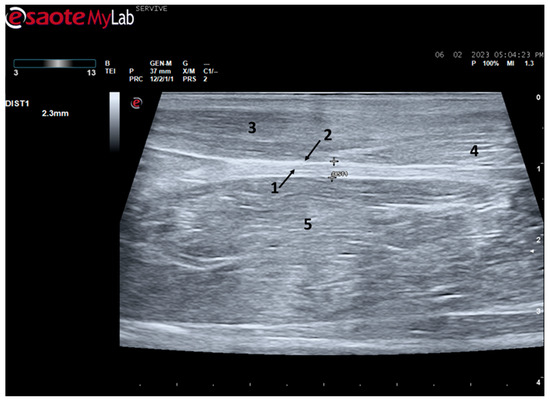

At the level of the greater ischiatic foramen, the sciatic nerve can be seen advancing between the dorsocaudal aspect of the acetabulum and cranial to the ischial tuberosity, passing over the muscle mass constituted by the gemelli and quadratus femoris muscles, close to the piriformis muscle and advancing caudally to the femur. The presence of these bony structures in the region, although they can be used as anatomical landmarks for nerve identification, can make a more proximal visualization difficult due to the curvature of the sciatic nerve and the hyperechogenicity of the bone that decreases contrast (Figure 3). Accompanying the nerve distally, it is visible between the muscles of the thigh, namely medially to the biceps femoris muscle, laterally to the adductor muscles, and caudally to the femur and the vastus lateralis muscle (Figure 4).

Figure 3.

Ultrasound image of the left sciatic nerve of a sheep after emergence from the greater sciatic foramen: (1) greater trochanter of the femur; (2) biceps femoris muscle; arrow—curvature of the sciatic nerve when passing between the reference bone structures. DIST1 represents the measurement of the diameter of the sciatic nerve.

Despite this, ultrasound has some disadvantages, starting with the fact that the nerves to be approached must have a superficial position in order to obtain images and details of greater quality. Nerves in a deeper position or very close to hyperechogenic structures, such as bones, make it difficult to obtain quality images with good contrast (Figure 3) [19]. Although it is a cheaper, less time-consuming, more accessible technique, and ultrasound scanners are more portable and easier to use routinely than the machinery of other techniques such as magnetic resonance imaging, ultrasound allows a lower contrast resolution. However, locally, ultrasound allows a better spatial resolution than resonance applied to the whole body [25]. Microscopically, ultrasonography does not allow an assessment of the anatomy and regenerative phenomena occurring at a subfascicular level, such as axonal and endoneurial growth, requiring the complementary use of stereological techniques.

The sciatic nerve was easily identified mid-thigh medially to the biceps femoris muscle and caudal to the femur and vastus lateralis muscle, allowing these muscles to be used as reference points for quick identification even for less experienced ultrasonographers. Monitoring the nerve in a proximal direction makes it possible to identify its passage between the greater trochanter of the femur and the ischial tuberosity, and these bony projections can be used as a reference point for its location. More proximally is its emergence from the greater sciatic foramen. At this level, the nerve may be more difficult to identify due to its curvature and also due to its proximity to the caudal gluteal artery and vein, but the use of a color-flow Doppler may clear up any doubts. Confusion with the sacred loin trunk in this region will be more unlikely since it is at greater depth. The sciatic nerve can also be easily tracked distally to the point where it branches proximally to the stifle. As the nerve progresses, an increase in echogenicity seems to be observed, a phenomenon described in other species [16], and which is probably related to an increase in the connective tissue within the nerve. It is important to remember that this increase in the amount of connective tissue is also related to an increased likelihood of compression or stretching injuries, making it harder to observe the nerve and apply local anesthetic blocks [26]. The mean diameter of the sciatic nerve measured mid-thigh and just before its branching site is identical to that indicated in other species, such as dogs of similar size. Its ultrasound appearance is similar to that described in other species, such as humans [27], dogs [14,15], or cats [16], appearing as a hypoechogenic tubular structure covered by a hyperechogenic envelope corresponding to the epineurium, an aspect that allows its easy differentiation from soft tissues and bones in the vicinity. Before its branching site, the sciatic nerve diameter was also measured in a cross-section, rotating the probe 45 degrees from the position that allows for obtaining the longitudinal image (Figure 8). Obtaining an image in this plane proved to be more complex and made it difficult to establish anatomical relationships with neighboring structures and with the ramifications of the sciatic nerve. On the other hand, the ultrasound image reveals characteristics identical to those obtained in the regular plane, in addition to the measured diameter being the same as that obtained with the previous technique. Therefore, it was decided not to use the transverse plane for this ultrasound characterization in any of the considered nerves.